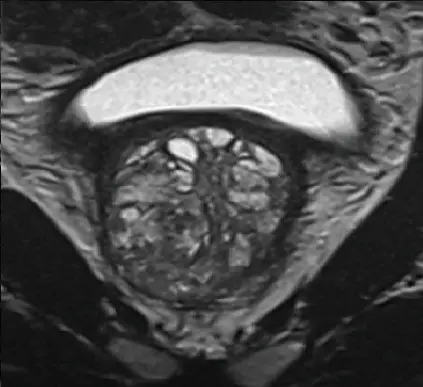

Prostatacarcinom (PIRADS4-Befund)

T2-Wichtung

Die Untersuchung umfasst verschiedene Bildsequenzen (=multiparametrisch), darunter:

• hochauflösende T2w- Aufnahmen (Beurteilung der Anatomie)

• diffusionsgewichtete Sequenzen (Beurteilung der Zelldichte)

• dynamische Kontrastmittelaufnahmen (Beurteilung der Durchblutung)

Diese Kombination ermöglicht eine sehr genaue Beurteilung nach international anerkannten Kriterien (PIRADS-Befundungsschema).